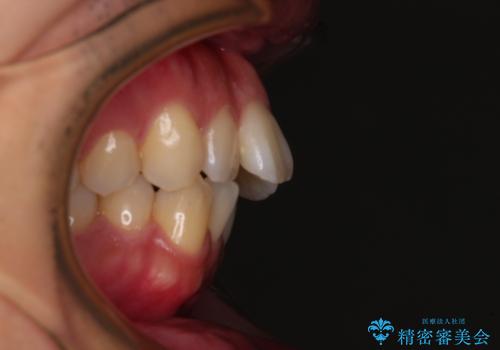

- 口元の突出感と下の前歯のがたつきを主訴として来院された患者様です。

口元の突出感と叢生改善のため上下左右の第一小臼歯4本を抜歯し、ワイヤー装置にて矯正治療を行うこととしました。